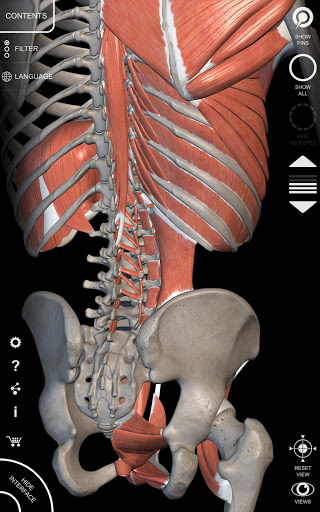

"Anatomía - Atlas 3D" permite estudiar la anatomía humana de forma fácil e interactiva.

A través de una interfaz sencilla e intuitiva es posible observar cada estructura anatómica desde cualquier ángulo.

Los modelos anatómicos 3D son especialmente detallados y con texturas de hasta una resolución de 4k.

La subdivisión por regiones y las vistas predefinidas facilitan la observación y el estudio de partes individuales o grupos de sistemas y las relaciones entre los diferentes órganos.

MODELOS ANATÓMICOS 3D

• Sistema musculoesquelético

nervioso • Sistema respiratorio • Sistema digestivo • Sistema urogenital (masculino y femenino) • Sistema endocrino • Sistema linfático • Sistema ocular y auditivo CARACTERÍSTICAS • Interfaz sencilla e intuitiva • Rotar y hacer zoom en cada modelo en el espacio 3D • Opción para ocultar o aislar uno o varios modelos seleccionados • Filtro para ocultar o mostrar cada sistema • Función de búsqueda para encontrar fácilmente cada parte anatómica • Función de marcador para guardar vistas personalizadas • Rotación inteligente que mueve el centro de rotación automáticamente • Función de transparencia • Visualización de músculos a través de niveles de capas desde las superficiales hasta las más profundas • Al seleccionar un modelo o un pin, aparece el término anatómico relacionado • Descripción de los músculos: origen, inserción, inervación y acción • Mostrar/ocultar interfaz de usuario (muy útil con pantallas pequeñas) MULTILINGÜE • Los términos anatómicos y la interfaz de usuario están disponibles en 11 idiomas: latín, inglés, francés, alemán, italiano, portugués, turco, ruso, español, Chino, japonés y coreano • Los términos anatómicos se pueden mostrar en dos idiomas simultáneamente REQUISITOS DEL SISTEMA • Android 8.0 o posterior, dispositivos con al menos 3 GB de RAM Reversi